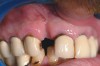

A 57-year-old woman presented seeking an implant-supported restoration to replace a failing bridge from her right maxillary second molar to her first premolar (Figure 7). Those teeth had been extracted traumatically more than 30 years ago.

Figure 7  Occlusal view before flap reflection.

Figure 7